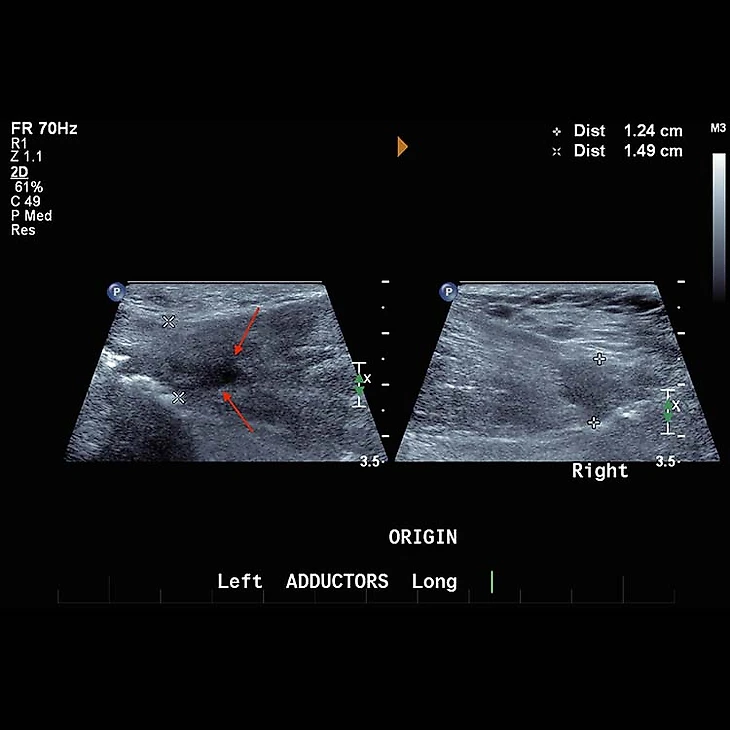

В больших клубах есть возможность провести УЗИ-диагностику. На экране мы можем увидеть нарушение структуры мышцы или сухожилия и гематому, если это острая травма. Так, например, будет выглядеть тендинопатия длинной приводящей мышцы – патология, при которой из-за перегрузки, частых травм или по иным причинам часть сухожилия замещается на соединительную ткань другого типа – не с такой однородной структурой и гораздо менее прочную. Единственным симптомом этого процесса будет все та же паховая боль.

Источник: FIFA medical Network

Справа здоровое сухожилие, мы видим нормальный ход волокон и однородную структуру. Слева же тендинопатия: темный участок – это как раз те самые структурные изменения в строении сухожилия. Похожая картина будет и при повреждении сухожилия.